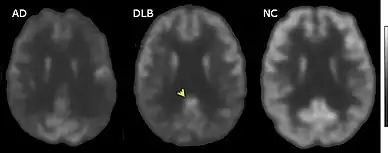

| Microscopic image of a Lewy body (arrowhead) in a neuron of the substantia nigra; scale bar=20 microns (0.02 mm) | |